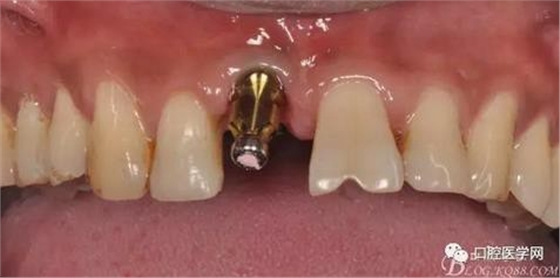

圖11 置閉口印模帽取模

圖19 口內(nèi)修復(fù)基臺(tái)正位照

圖20 口內(nèi)修復(fù)基臺(tái)正位照